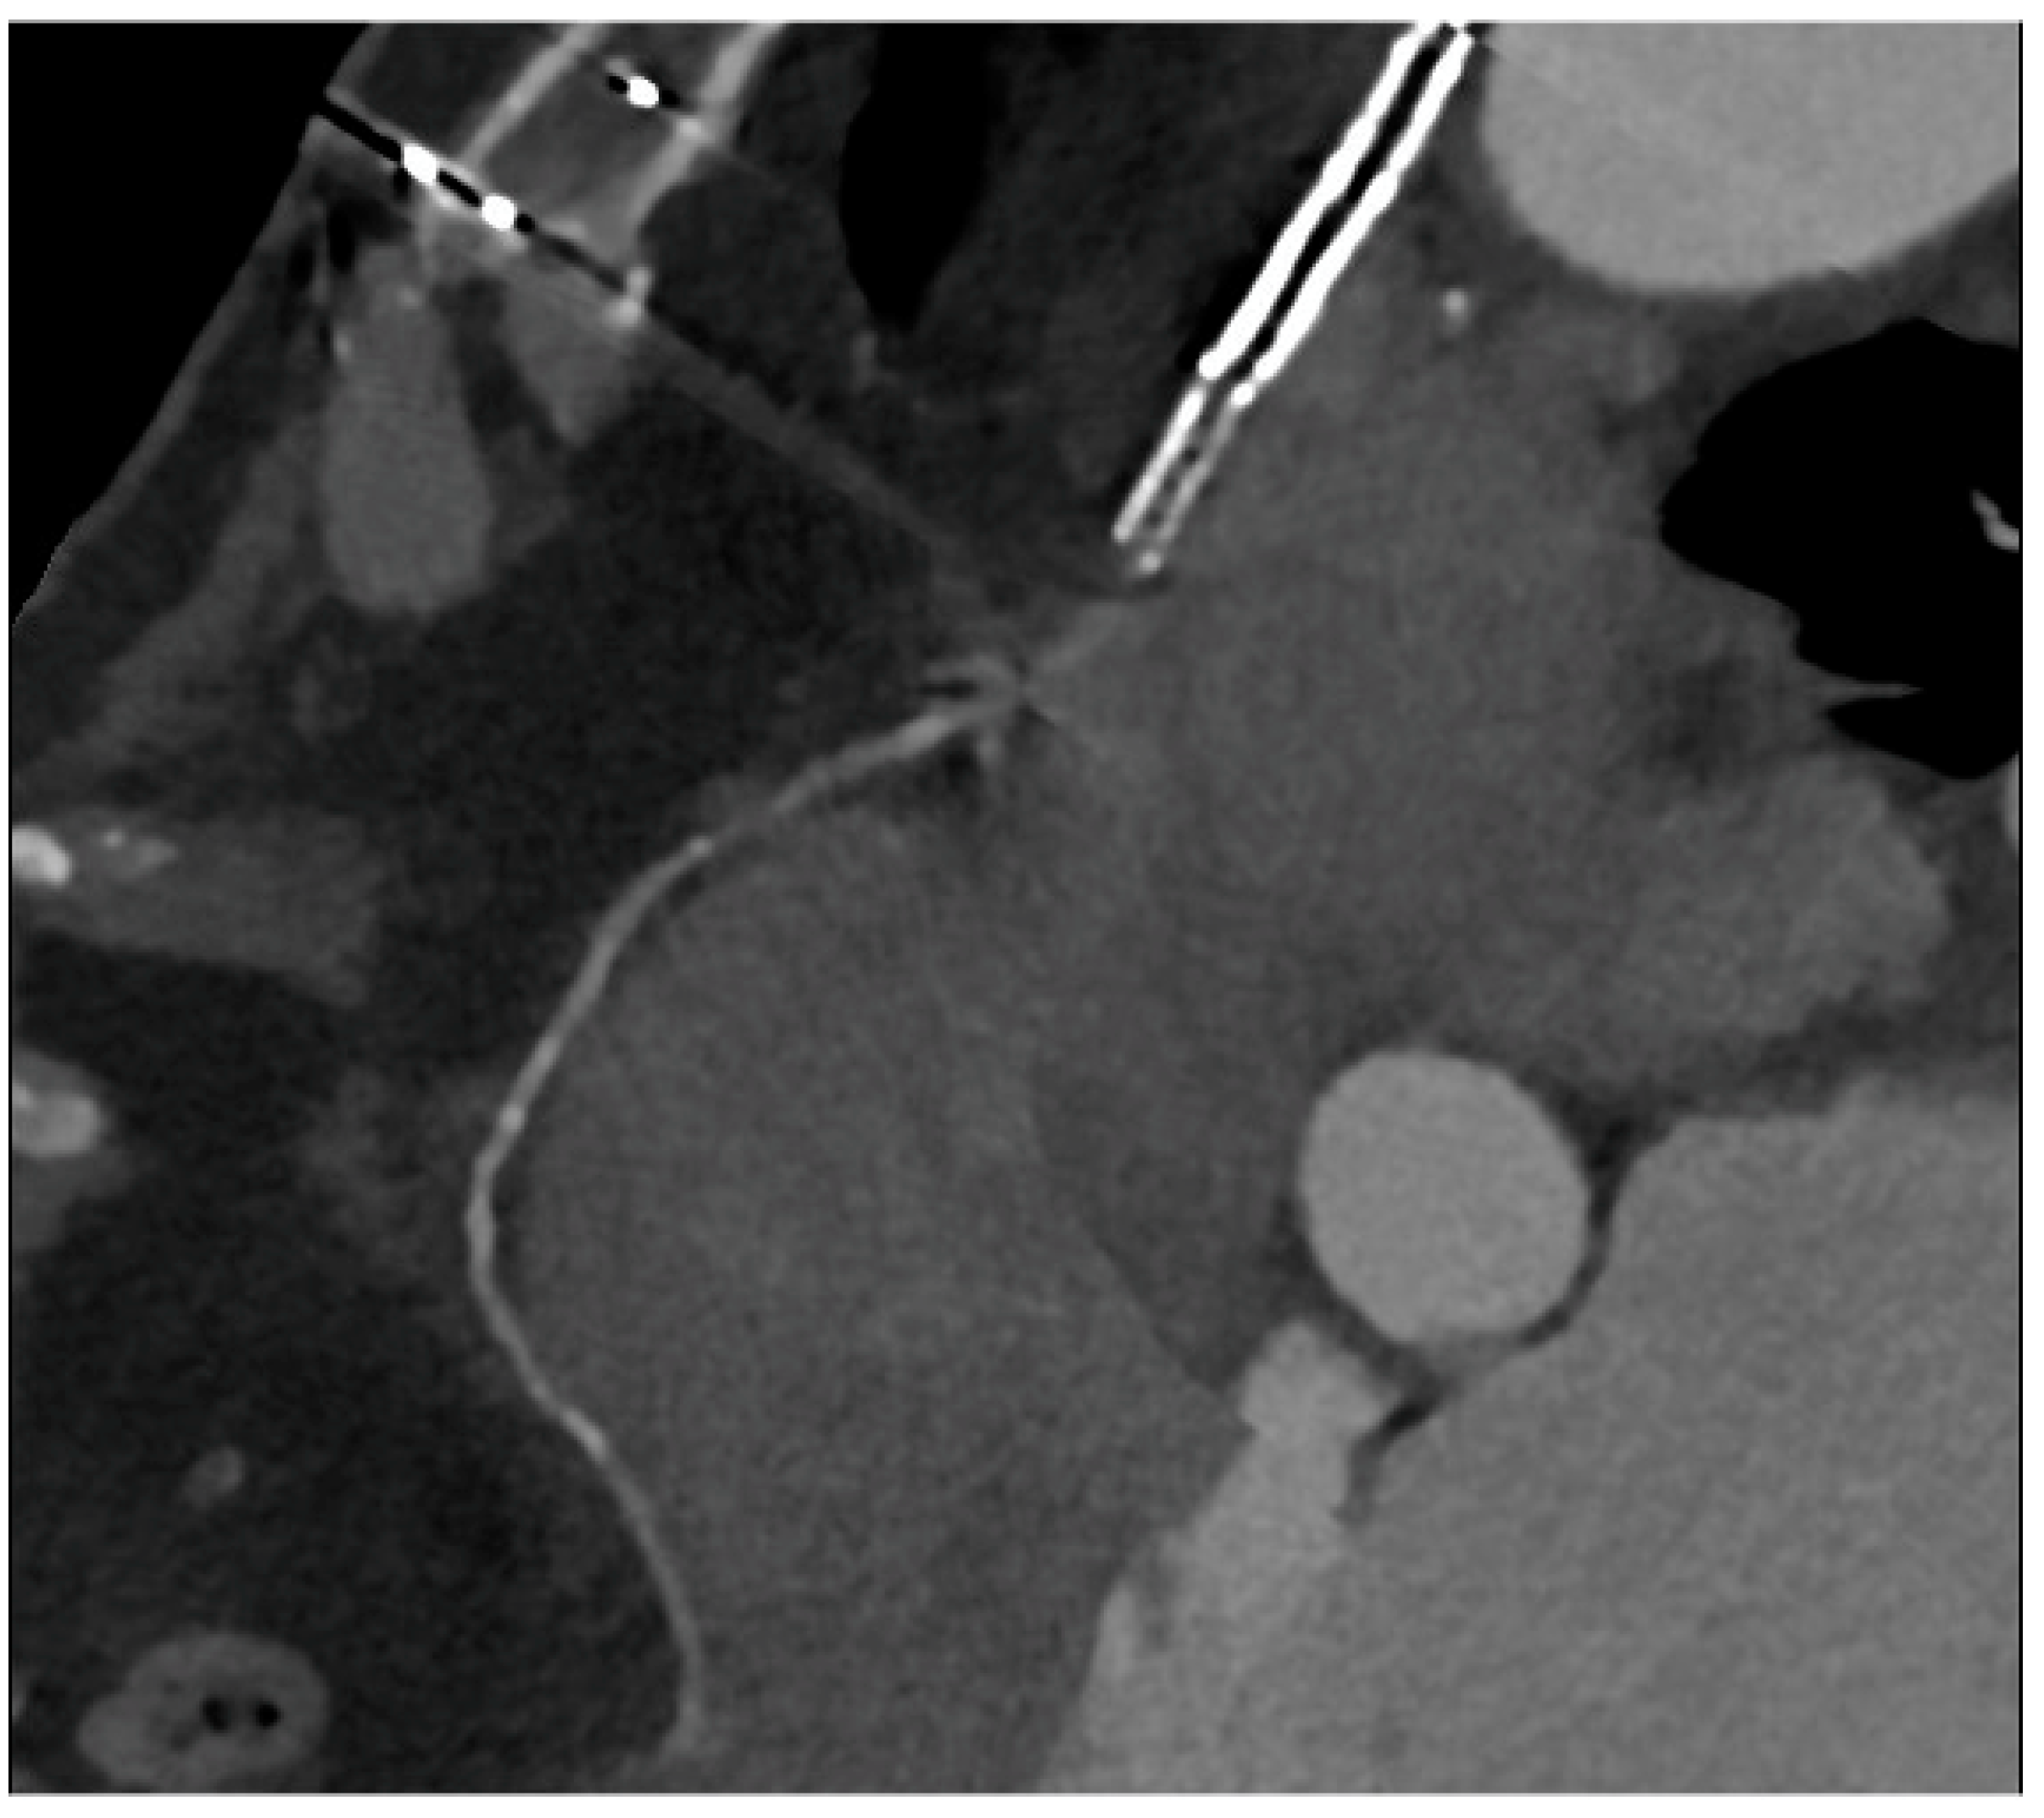

Figure 5.

In (A,B), two multiplanar reconstructed images of the left internal mammary artery CABG on the left anterior descending coronary artery. There are no signs of degenerative disease with the patency of grafts.

Figure 6.

An occluded saphenous vein graft to the right coronary artery. The graft was previously treated with a stent, which appears occluded.